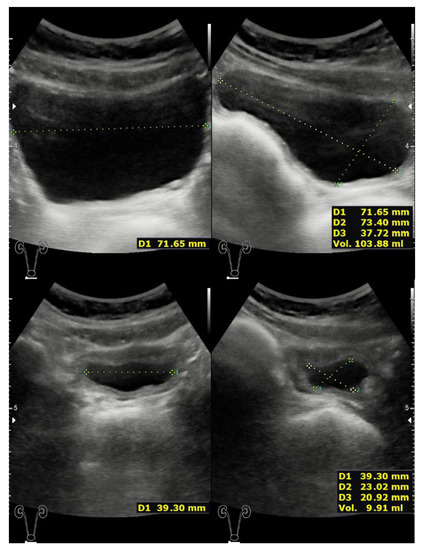

2. Case Presentation

2.1. Case 1

2.2. Case 2